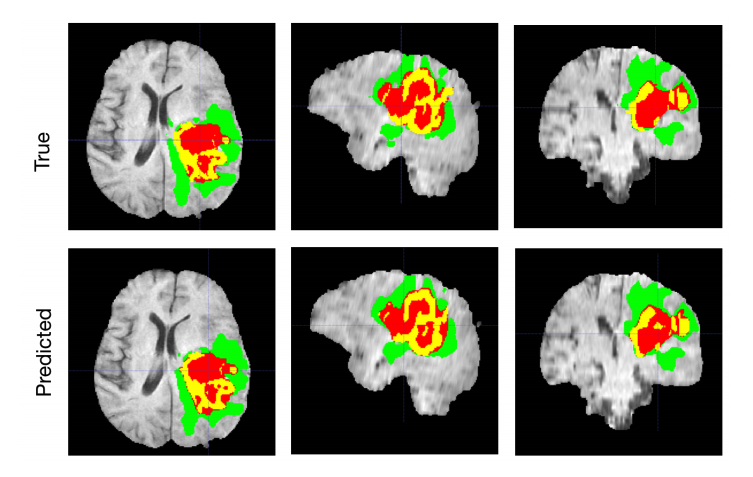

Brain Tumor Segmentation

AI · Healthcare

2023 · Lead Researcher

Automated detection, segmentation, and characterization of brain tumors from multimodal MRI using advanced deep learning architectures. It aims to improve diagnostic accuracy and support clinical decision-making by enabling robust, efficient, and clinically deployable neuroimaging analysis..

Estimation of uncertainty in Brain Tumor segmentation using modified multistage 3D-UNet on multimodal MRI images.

Bhavesh Parmar, Mehul Parikh

Brain Tumor Segmentation and Survival Prediction Using Patch Based Modified 3D U-Net.